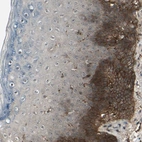

Immunohistochemical staining of human lymph node shows strong membranous and cytoplasmic positivity in non-germinal center cells.